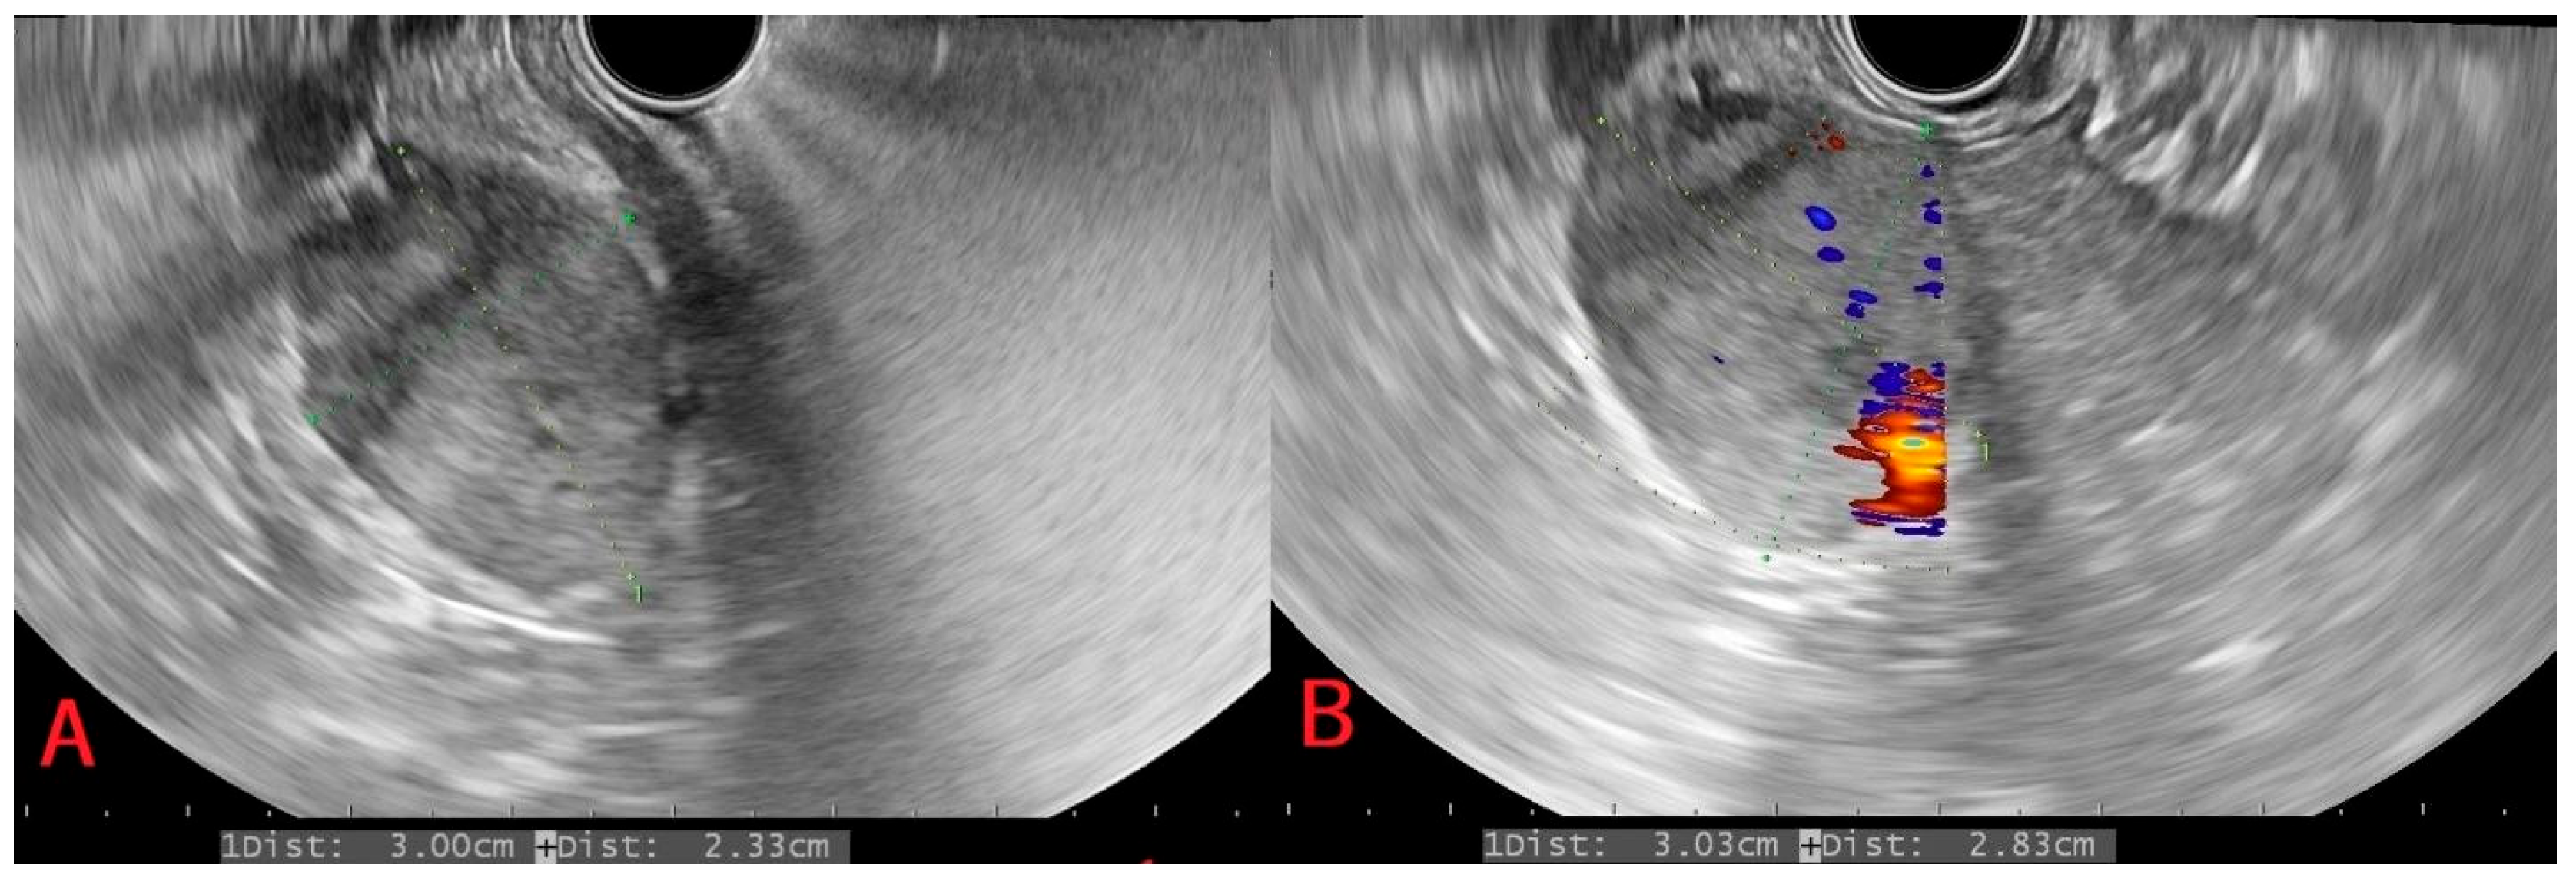

| 4 | 78/F | Recurrent UGIB which revealed a pancreatic lesion bulging and infiltrating in the second part of the duodenum and an anatomic vascular variant with a replaced right hepatic artery arising from the superior mesenteric artery; history of ccRCC (more than 20 years prior, grade 2, surgically managed); simultaneously diagnosed sigmoid adenocarcinoma (due to the appearance of wall thickening on CT). | Pancreatic lesion bulging and infiltrating in the second part of the duodenum. | Irregular, round, intense Doppler vascular signal, hard consistency. | Limited IHC evaluation, but PAX8 positive | Recurrent hemorrhagic episodes. | Endoscopic hemostasis with initial inconclusive biopsy→CT→EUS with FNA→ left colectomy and cephalic duodenopancreatectomy; favorable outcome maintained at 2-year follow-up. |